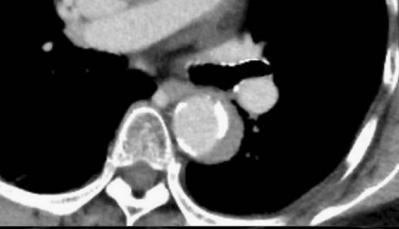

下图的胸部CT平扫,有什么大问题?

图4

仔细一看,主动脉里面有线样高密度阴影!这个要高度警惕主动脉夹层!

图5